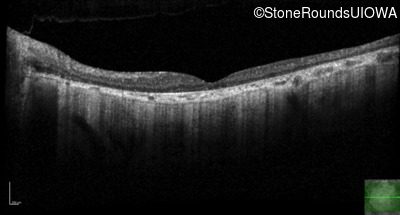

Optical Coherence Tomography - Right - 20/250 sc

Exemplar / OCT Stack